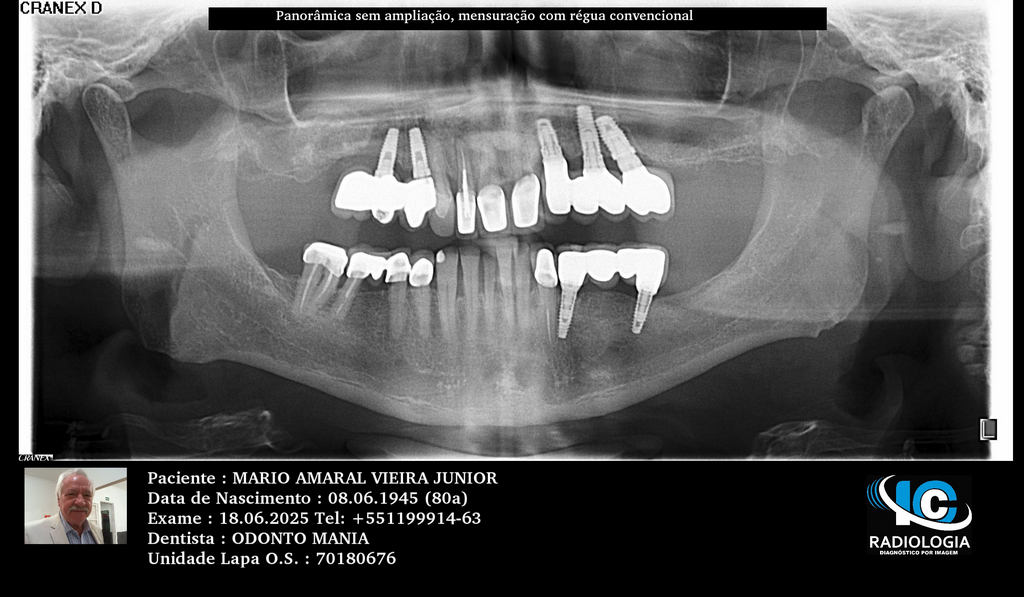

PRÓTESE TOTAL FIXA EM IMPLANTES

M.A.V.J.